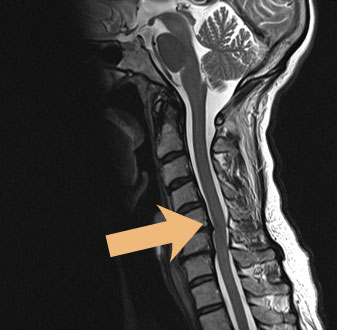

Um die Spinalstenose von anderen Erkrankungen abzugrenzen, die ähnliche Beschwerden verursachen, werden Patienten zunächst neurologisch-orthopädisch untersucht inklusive einer umfangreichen Anamneseerhebung. Im Anschluss daran werden häufig bildgebende Untersuchungen wie die MRT durchgeführt. Mit der Magnetresonanztomographie lassen sich Spinalstenose und andere Erkrankungen der Wirbelsäule sehr gut untersuchen und sichtbar machen. Auf dem MRT-Bild links erkennt man eine Spinalstenose in der Halswirbelsäule, die den Spinalkanal über mehrere Segmente hinweg einengt.

In der Beta Klinik verwenden wir einen offenen MRT, der es uns bei der Diagnostik der Spinalstenose HWS ermöglicht, auch klaustrophobische Patienten oder solche bis 250 kg komfortabel zu untersuchen.